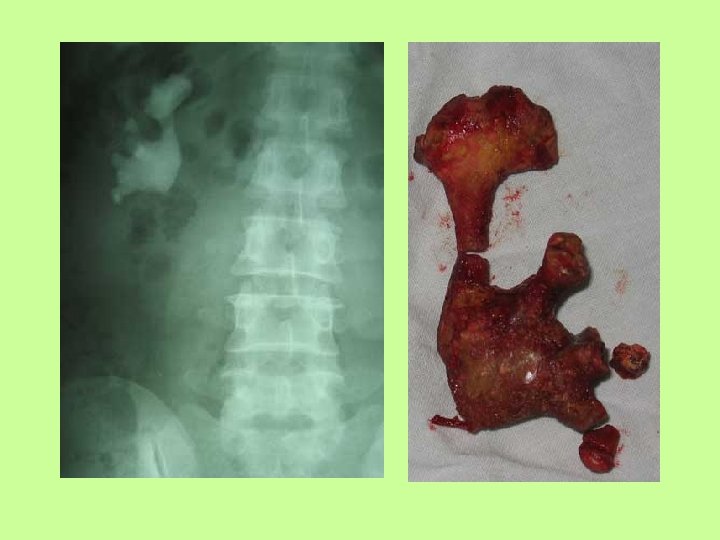

Urinary Conditions • Kidney Stones – Also called Renal Calculi – Solid crystals that are formed from ions in urine – Can be the size of grains of sand up to golf -ball sized – As small as 2 -3 mm can block the ureters

Urinary Conditions • Kidney Stones, con’t – Usually detected by an X-Ray or Ultrasound – Some small stones may pass on their own – Larger stones must either be broken up with Shock Wave Lithotripsy or be removed with surgery

• FYI: Stones can look different depending on what ions precipitated out! • http: //www. herringlab. com/photos/